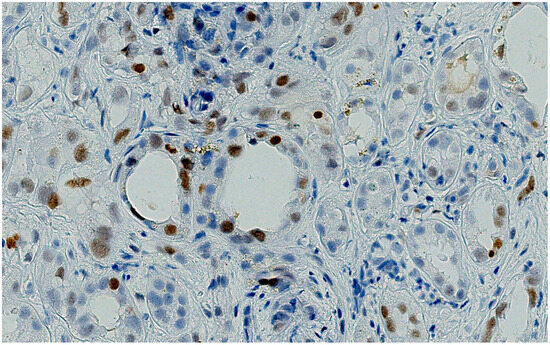

The patient developed nephrotoxicity after the second cycle, for which renal biopsy was performed. Renal biopsies showed no glomerular proliferative lesions, and electron microscopy did not reveal any electron-dense deposits. Severe tubular damage, characterized by the loss of the brush border, flattening of the epithelium, vacuolization, and tubular distalization with focal tubular necrosis were present together with signs of tubular regeneration such as cariomegalia and mild atypia. The underlying chronic renal damage was mild to moderate, with interstitial fibrosis and tubular atrophy not exceeding 10%. No significative lymphocyte infiltration was observed, and the immunohistochemical assessment of PDL-1 was negative. It was noteworthy that the antibody anti-p53 showed a patchy moderate-to-strong staining of the nuclei of proximal renal tubules (Figure 1, Figure 2, Figure 3 and Figure 4).

A thorough morphological examination including electron microscopy can assist a nephropathologist in distinguishing between ATN and AIN lesions with greater precision. However, both drugs can cause both pathological patterns, making it necessary to use advanced immunohistochemical techniques to determine which drug is responsible for the nephrotoxicity. In our case, the tubular expression of anti-PD1 was negative, while the tubular expression of p53 was positive.

The pattern of p53 expression is negative in unstimulated cells. However, in stimulated cells, there is patchy weak-to-moderate nuclear positivity. Mutated p53 results in diffuse, moderate-to-strong nuclear positivity [26].

Figure 2. The same nuclei showed a brisk nuclear immunostaining for P53 (DAB. X200.P53 NEW).